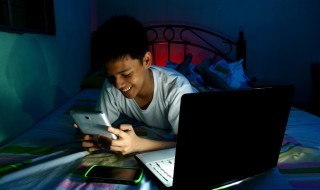

‘Night owl’ teenagers at heightened risk of tooth decay

New research suggests that adolescents who prefer to stay up late at night are at a significantly higher risk of…